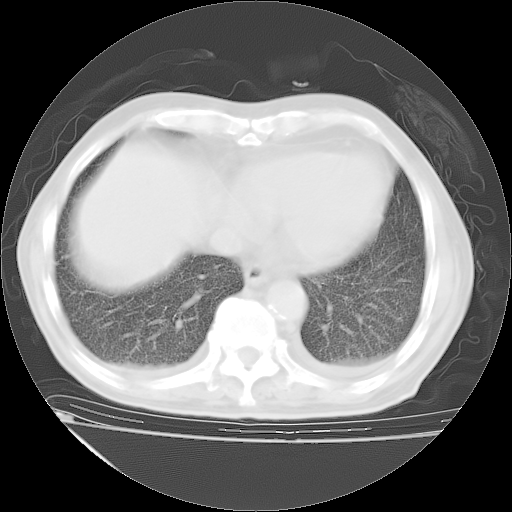

经过24天治疗,岳父的病情基本稳定。生活基本可以自理,可以下床活动。呼吸困难早已消失。体温基本正常。

只是甲强龙用80mg时血小板升到正常,改为60mg后又降到63×10*9/L。

主要治疗甲强龙80mg×14天,60mg×10天;同时抗结核(异烟肼+利福平+乙胺丁醇)。环磷酰胺0.1 tid 10天。

特别感谢胡教授、高管、桃子版主给出关键的治疗建议。桃版把所有肺部影像和全部临床资料请所在医院呼吸科、感染病科、结核科、临床免疫科专家会诊。临床免疫科专家制定了完整的治疗方案。